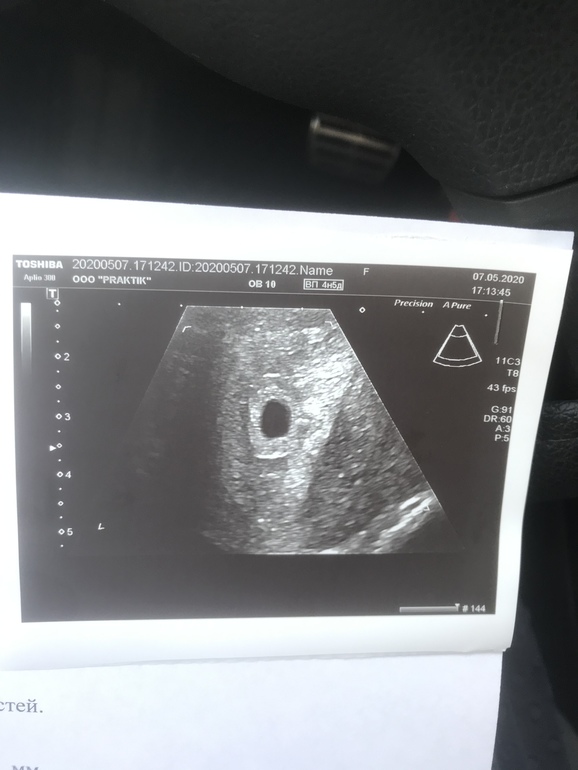

БеременностьНу вот я и сходила на наше первое УЗИ, попасть даже в платную клинику в условиях карантина было не просто, потому что некоторые клиники записывают аж на конец мая, ну это очень долго ждать. Все таки я нашла клинику и пошла в этот же день. По результатам УЗИ обнаружили маточную беременность срок 4-5 недель и дали фото нашего будущего малыша)))